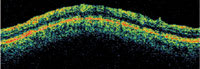

The HRT3 shows a 3-D image of the optic disc. The green line outlines the disc margin. |

The GDx measures the retardance of polarized light as it travels through the retina and shows five major components of the affected eye. Left: normal eye; right: glaucoma eye. |

| ■GDx, Carl Zeiss Meditec. The

scanning laser polarimeter measures the phase shift of polarized light passing through

the eye. It measures the retinal nerve fiber layer (RNFL), in a 20� x 20� area

around the optic disc. It aids in diagnosis and management, particularly for risk

factors such as large cups or elevated pressures that exist without visual field

defects.The GDx also compares RNFL measurements to a large database and provides

graphic images for early diagnosis and tracking change over time. Dimensions H:

14"; W: 10". ■HRT3, Heidelberg Engineering. Confocal scanning laser ophthalmoscope provides 3-D topographical image of the width, depth and rim slope of the optic disc as well as the RNFL; it also provides Glaucoma Probability Score and progression analysis. The HRT3 provides probability values for damage consistent with glaucoma, as well as information on the integrity of the neuro-retinal rim and RNFL. Scan field (actual image): 15� x 15�. Dimensions H: 36"; W: 23". ■Model MHF-1, Portable Ophthalmic Devices. This is a high-frequency imaging system for anterior and posterior chambers; it documents the anterior angle without contact, using a self-contained water bath probe. It captures images through high-frequency ultrasound and provides an ultrasonic view of the angle and pathology of the eye. The company expects FDA-approval for the U.S. human market this year. Dimensions H: 12"; W: 9". ■SL OCT, Heidelberg Engineering. Images and monitors angle status; provides non-contact, high resolution analysis of anterior segment. It's similar to a sonogram, but uses 1300 nm of laser light, so it's non-contact. It views and evaluates virtually any anterior segment or tissue and provides angle assessment and measurement. Dimensions H: 24"; W: 36". ■Stratus OCT, Carl Zeiss Meditec. It uses near-infrared frequency light (82 nm) to scan the retina. This is similar to ultrasound, but uses a broad bandwidth light beam instead of sound and does not require contact with the tissue. The device provides a structural RNFL as assessment aids in early diagnosis and monitoring progression. The Stratus images and measures the optic nerve head and RNFL. Its RNFL analysis enables objective measurement of peripapillary RNFL thickness. Dimensions H: 50"; W: 48". ■Visante, Carl Zeiss Meditec. It provides non-contact visualization of the anterior chamber using 1310nm of light with optical coherence tomography. It provides a large field of view, optimized for the anterior chamber. Detailed images of the anterior angle, including the scleral spur, are helpful for diagnosing and managing narrow angle glaucoma. The visualization of blebs and implants aid in glaucoma treatment planning and management. Dimensions H:19.09"; W: 17.24". |